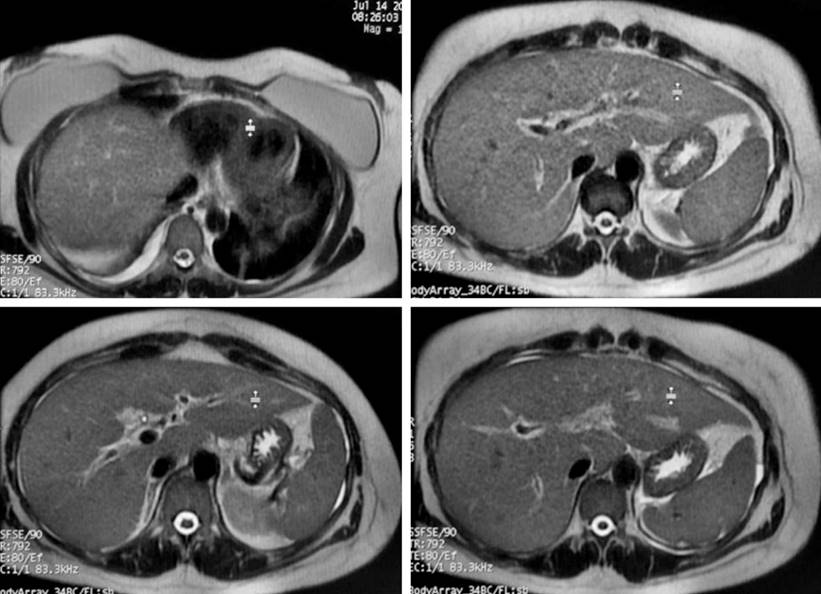

After the liver and bile duct ultrasound, hepatic steatosis, cholecystitis, and biliary sludge were detected. Consequently, the surgeons assessed the patient and requested both abdominal tomography (Figure 1) and magnetic resonance cholangiopancreatography (Figure 2). However, as hyperbilirubinemia persisted at the expense of direct hyperbilirubinemia, gastroenterologists performed an endoscopic retrograde cholangiopancreatography (ERCP). The ERCP revealed the papilla of Vater in the second flat duodenal portion, selective admission to the bile duct with bow papillotome plus hydrophilic guide. In addition, the contrast-enhanced cholangiography confirmed a normal caliber bile duct without stones, exploration of the bile duct with Dormia basket and extraction of biliary sludge and retained bile, and bile duct washing until clear bile drainage.